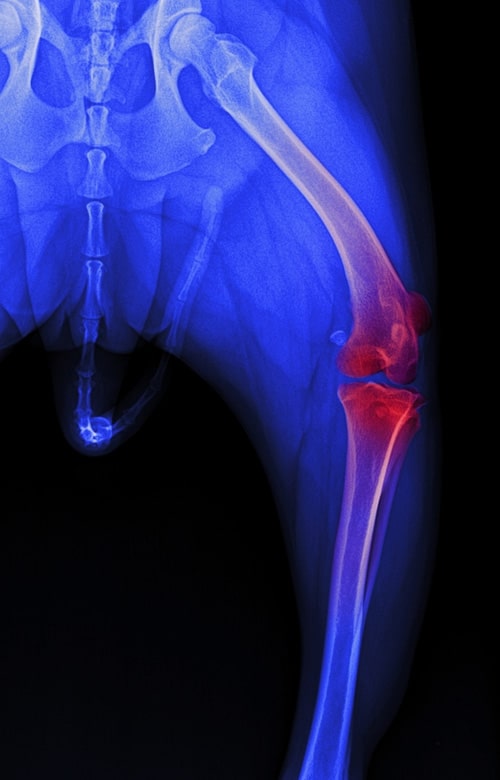

Medial Patellar Luxation Repair Medial Patellar Luxation occurs when the kneecap shifts to the inside of the leg, which is most common in small-breed dogs. It can cause intermittent limping, skipping, or hopping on the affected leg, sometimes accompanied by a clicking sound. Surgical correction realigns the kneecap, improving comfort and mobility. A consultation will help us determine the severity of the condition and the best treatment plan for your pet.